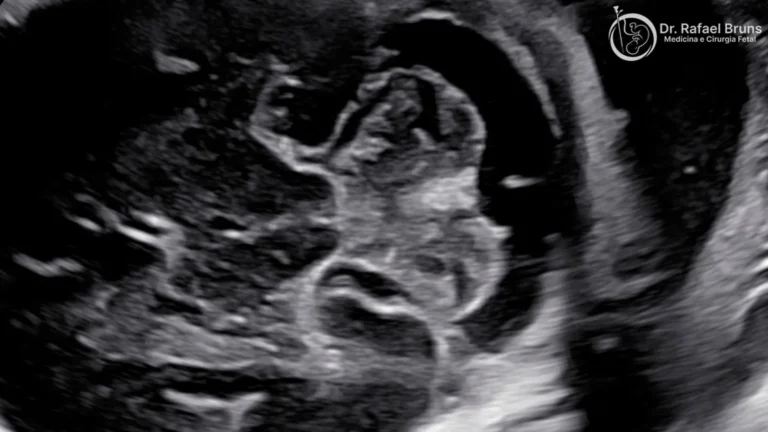

O ultrassom obstétrico convencional produz imagens de estruturas — o bebê, a placenta, o cordão, o líquido amniótico. Você vê a anatomia. O Doppler acrescenta uma camada a isso: ele detecta o movimento das células do sangue e calcula a velocidade e a direção do fluxo dentro de um vaso específico.

Doppler colorido (ou color Doppler): mapeia o fluxo em toda uma região ao mesmo tempo, colorindo os vasos conforme a direção do sangue — vermelho para um sentido, azul para o outro. Ele é fundamental para localizar vasos, identificar estruturas cardíacas fetais, avaliar o cordão umbilical e orientar a medição espectral. No exame do coração fetal, o Doppler colorido permite visualizar como o sangue se move pelas câmaras e válvulas com precisão impossível de obter só com a imagem em escala de cinza.